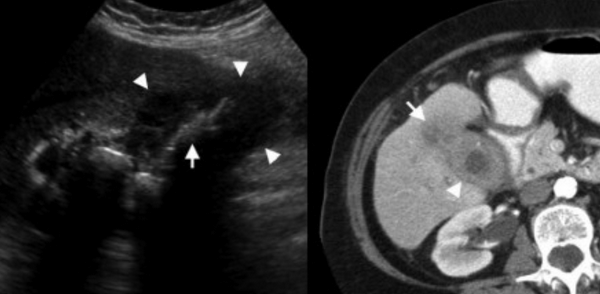

Ксантогранулематозный холецистит — это воспалительное заболевание, характеризующаяся тем, что в стенке желчного пузыря образуются ксантомы и гранулемы. При исследовании выявляют утолщение стенки желчного пузыря, уменьшение органа в размере, а также интрамуральные узелки, которые визуализируются, как гипоэхогенные включения на УЗИ и гиподенсные на компьютерной томограмме. Данные включения схожи с включениями при карциноме желчного пузыря.

УЗИ и КТ желчного пузыря. Ксантогранулематозный холецистит. Слева на УЗИ визуализируется (помечено стрелками) утолщение стенки желчного пузыря с интрамуральным включением и с камнем в просвете органа. Справа на КТ выявляется утолщение стенки с гиподенсными включениями.